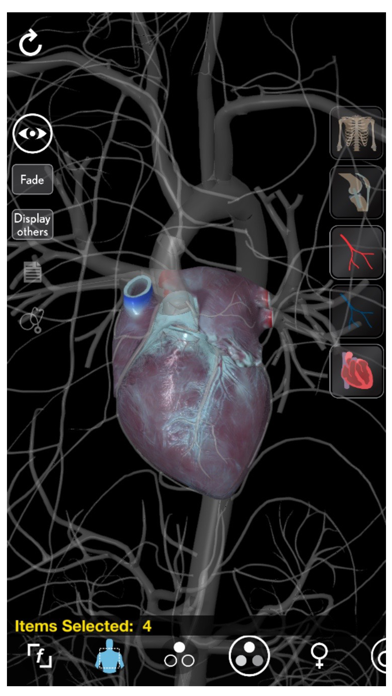

3. The 3D anatomy models can add important cognitive input for understanding the spatial relationship between anatomical structures and landmarks leading to an increased retention of knowledge.

5. Learn heart and vascular anatomy with thousands of realistic anatomical models/structures.

10. + Beautiful symmetry of designed organs and structures makes learning easy and pleasant.

11. + Visualize anatomy using the latest 3D technologies.